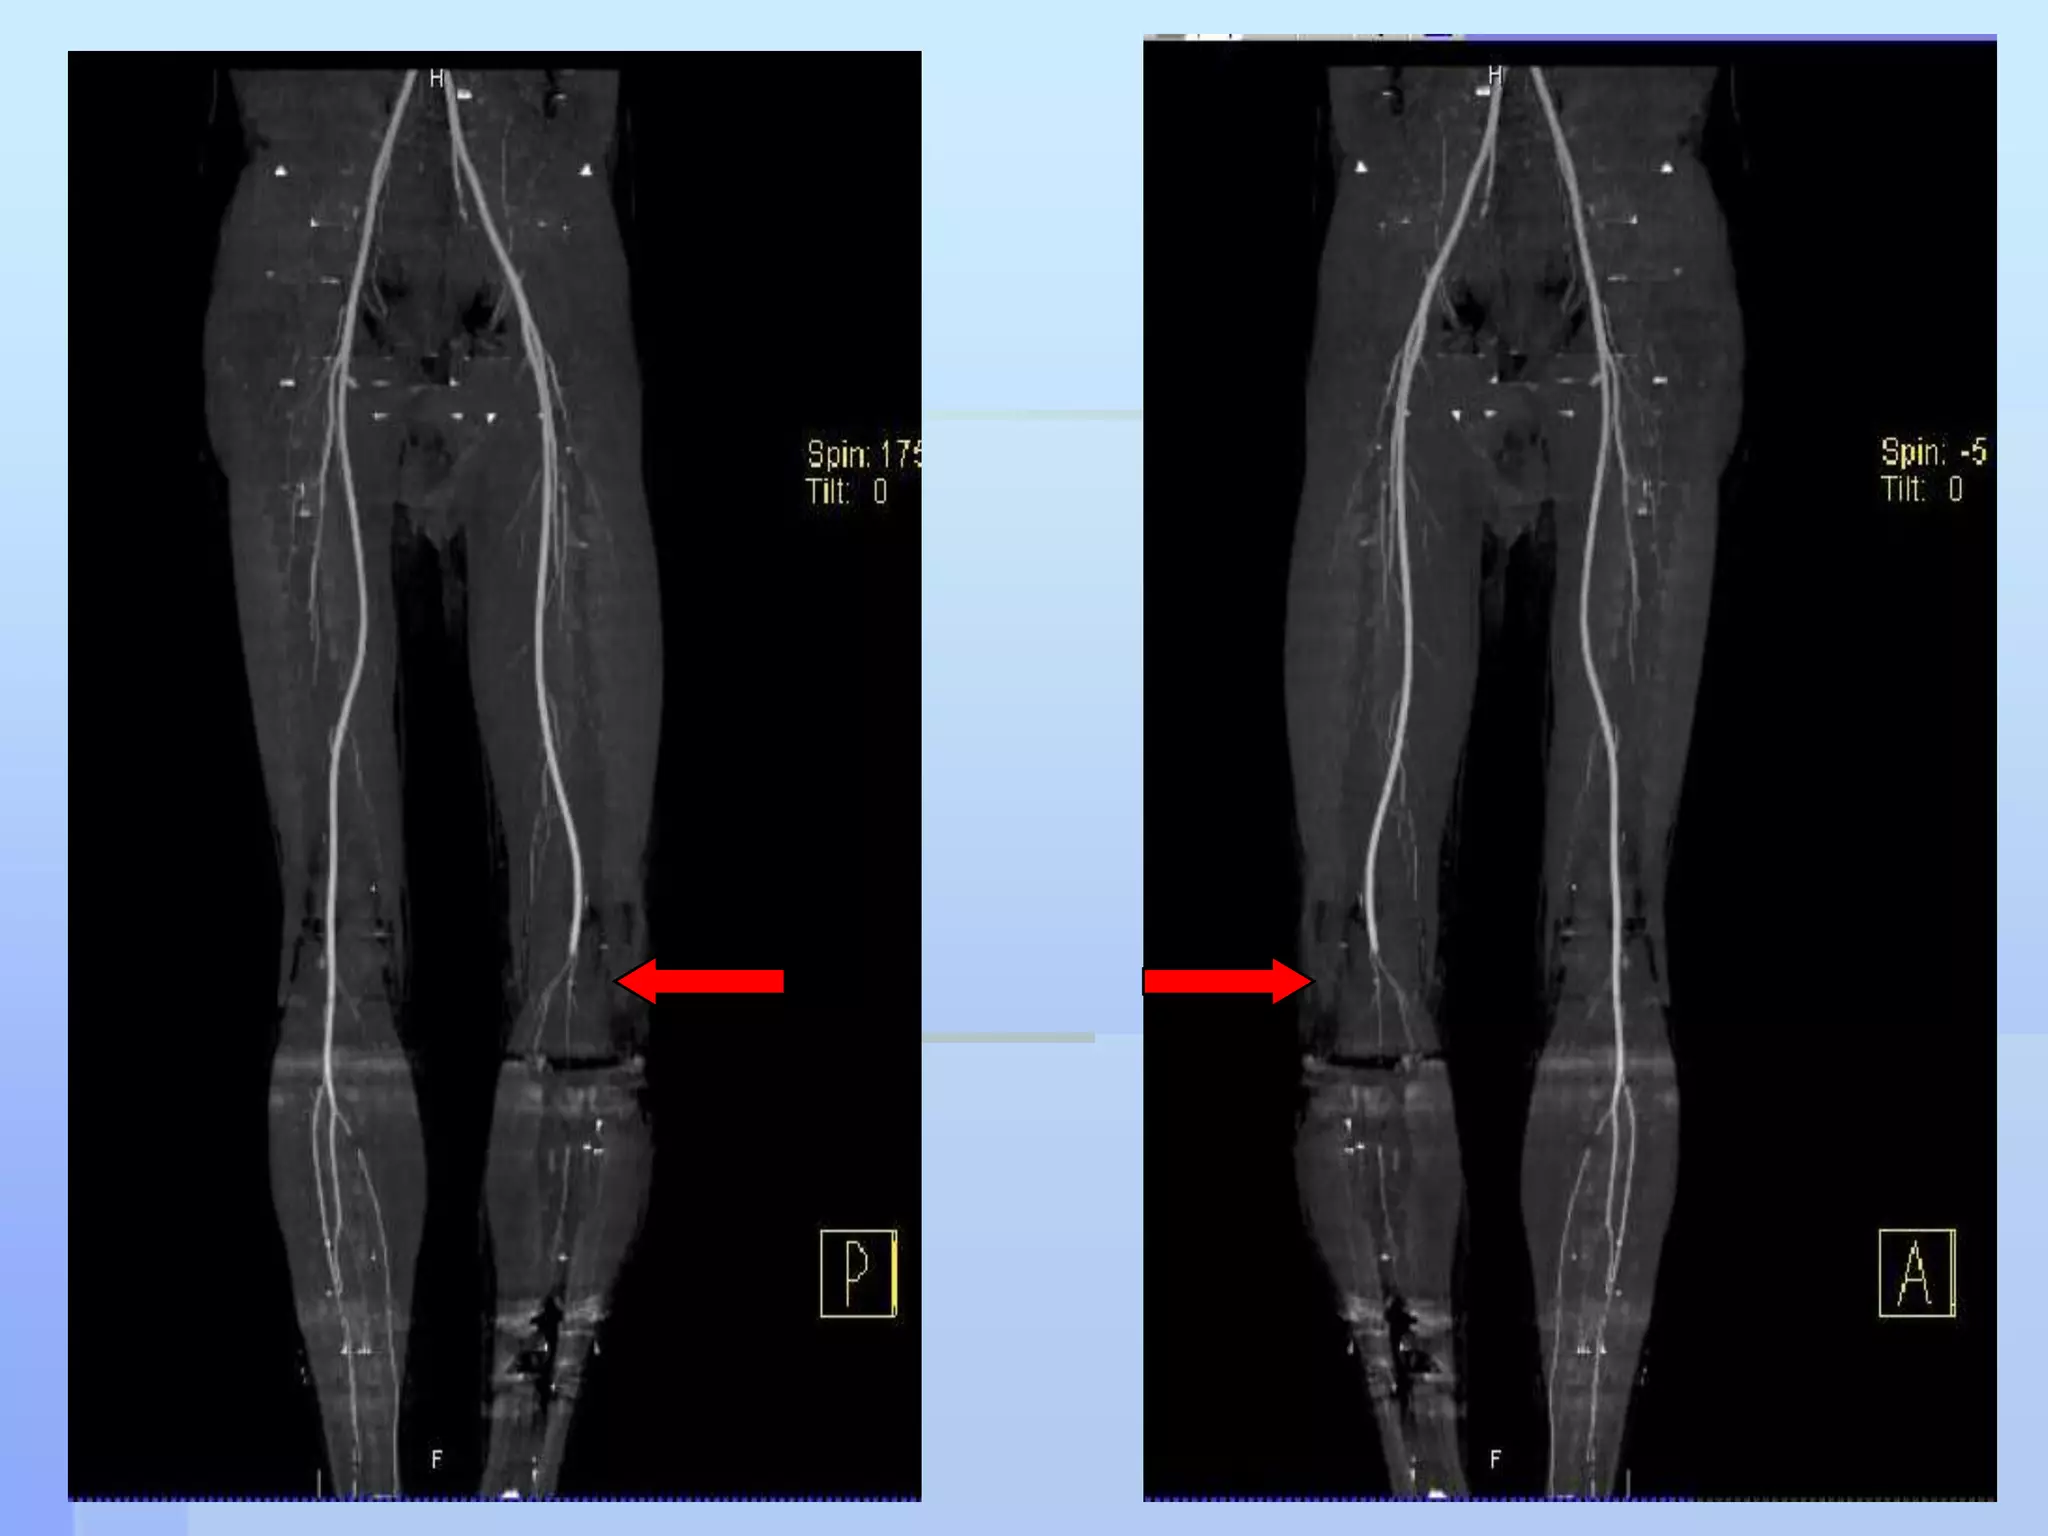

CT angiogram was doneIt showed Vascular injury @ the level of             segment 2 of the Popliteal arteryNo distal run off

CT angiogram wasdoneIt showed Vascular injury @ the level of segment 2 of the Popliteal arteryNo distal run off